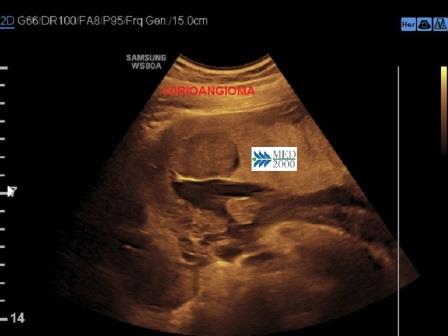

All'esame ecografico il corioangioma si presenta come una massa rotondeggiante, ben delimitata, ipoecogena o mista, di diametro variabile da 1 a 5 cm.

E' in genere localizzato vicino alla inserzione del cordone ombelicale sulla superficie fetale della placenta, spesso può sporgere in cavità amniotica.